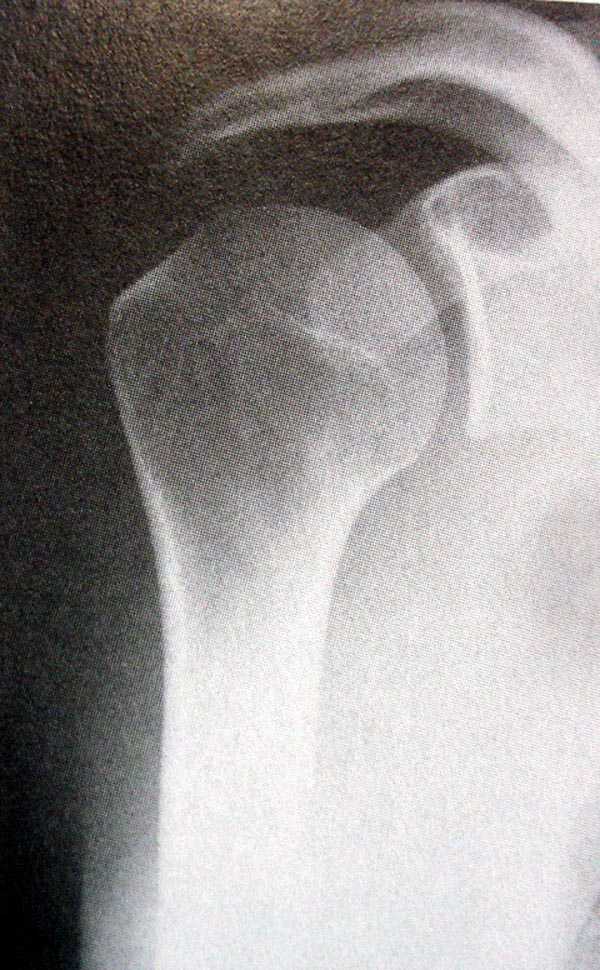

Проблема -- смещение отломка, неудовлетворительный контакт, угроза нарушения функциональности (ограничение движений, если срастется так). Мнения разделились примерно пополам: лечить консервативно/прооперировать. Кроме того, пациент жалуется на сильные боли в суставе, которых, как мне кажется, на пятнадцатый день быть не должно.

Нельзя по одной проекции судить о положении отломков

Рентгенологические исследования проксимального отдела плеча состоит из прямого, бокового и аксиальных видов. Если имеются сложные переломы тогда рекомендуется Томография, а так в большинстве случаев достаточно бывает стандартных снимков.

Независимо от условий (нежелание рентгентехника или отсутствие пленок) необходимо добиться рентгенограмм, особенно аксиальной, потому что одна проекция не гарантирует, что не пропущен вывих в плечевом суставе.

Для принятия решения и исследования обычно достаточно пару дней, а здесь третья неделя, начало консолидации метафизарной части, надо спешить!